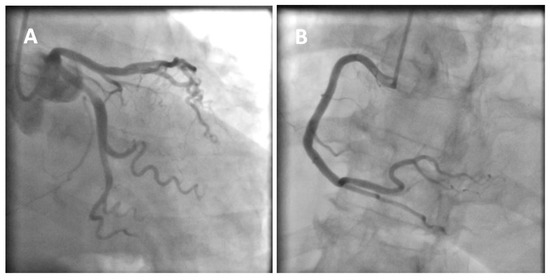

Figure 1. A 77-year-old obese woman with approximately 20 h of retrosternal pain was admitted to the clinic with suspected inferior STEMI infarction. The patient suffered from COVID-19 for four weeks before admission. On admission to the clinic, the patient reported chest pain. The ECG showed atrial fibrillation with a frequency of QRS about 100/min and ST-segment elevation in I, II, III, aVF, and V2-V6. The patient underwent coronary angiography, which revealed parochial atherosclerotic lesions in the coronary arteries (A,B) and, in the aortography, there were no signs of aortic dissection. The echocardiography showed normal valves function, good left ventricular systolic function with 58% ejection fraction (LVEF), and the presence of fluid in the pericardial sac, up to 10–11 mm behind the lower ((C), white arrow) and lateral ((D), yellow arrow) walls. The laboratory tests showed increased parameters of inflammation and normal levels of troponin and cardiac enzymes. Pericarditis was diagnosed and a treatment was started with colchicine, ibuprofen, enoxaparin, ceftriaxone, and levofloxacin. On the second day of hospitalization, the clinical condition of the patient deteriorated. There was an increase in renal parameters (creatinine—1.45 mg/dL, urea—100.5 mg/dL, and eGFR—37 mL/min) and atrial fibrillation with a fast QRS rate of 150/min. Pulmonary edema occurred, which was controlled by the intravenous infusion of furosemide and nitroglycerin. An echocardiogram was performed, which showed no significant changes. On the next day, the patient had a further deterioration in renal function with anuria. Hemodialysis was performed, followed by a return to diuresis. In the following days of hospitalization, the clinical condition of the patient improved. An echocardiographic examination was repeated in the patient every 1–2 days, confirming the good systolic function of the left ventricle and a constant amount of fluid in the pericardial sac. On the sixth day of hospitalization, the patient experienced a sudden cardiac arrest in the ventricular fibrillation (VF) mechanism. Resuscitation activities were undertaken, obtaining an atrial rhythm of about 90–100/min. In addition, the electrocardiogram showed a right bundle branch block and left bundle branch posterior bundle block (RBBB + LPH), QTc—510 ms. The patient was connected to a respirator and administered dobutamine, noradrenaline by continuous intravenous infusion, and amiodarone. The echocardiography revealed extensive abnormalities of contractility with akinesis of the apex, apical, and middle segments of all left ventricular walls, which may be consistent with Takotsubo syndrome (E,F). The ejection fraction was estimated at approximately 15%. There was a small amount of fluid in the pericardial sac. After a few hours, the patient returned to sudden cardiac arrest by VF and pulseless electrical activity (PEA). The resuscitation measures undertaken turned out to be ineffective, and the patient was pronounced dead. Patients with cardiovascular diseases are at risk of a severe course of COVID-19, as they are at risk of exacerbation of existing cardiological diseases and a higher risk of complications. Cardiological complications also often occur in COVID-19 patients with no previous history of cardiac diseases [1]. Pericarditis occurs in 3% of patients with COVID-19. The main symptom of pericarditis is retrosternal pain; ECGs show diffuse ST-segment elevations and echocardiography shows a small amount of fluid in the pericardial sac and elevated parameters of inflammation. The prognosis of patients is usually favorable [2]. The literature data on Takotsubo syndrome in COVID-19 is limited, but to date it has been noticed that a small percentage affects women, who constitute 50–60% of the groups of patients (90% before COVID-19). The more frequent stressor causing TS is the physical factor [3,4]. The diagnosis of Takotsubo syndrome in COVID-19 is significantly difficult and is often based on echocardiography and the probability of Takotsubo according to the InterTAK scale [5]. The prognosis of patients is unfavorable, and mortality is about 30–40%. Takotsubo syndrome with severe arrhythmias and acute heart failure was the direct cause of death of our patient. The patient’s condition required the use of inotropic drugs, which probably did not improve her prognosis. Currently, in TS with cardiogenic shock, the use of levosimendan is recommended and mechanical circulatory support should be considered (intra-aortic balloon pump, Impella or ECMO) [6,7]. Various cardiac complications in both acute COVID-19 and later post-COVID syndromes worsen the prognosis of these patients. The number of stress factors associated with falling ill with COVID-19 increases the risk of Takotsubo syndrome. The differences in Takotsubo syndrome in COVID-19, demonstrated to date, require confirmation in subsequent prospective studies and discussion on the verification of the criteria for diagnosing TS in patients with COVID-19.